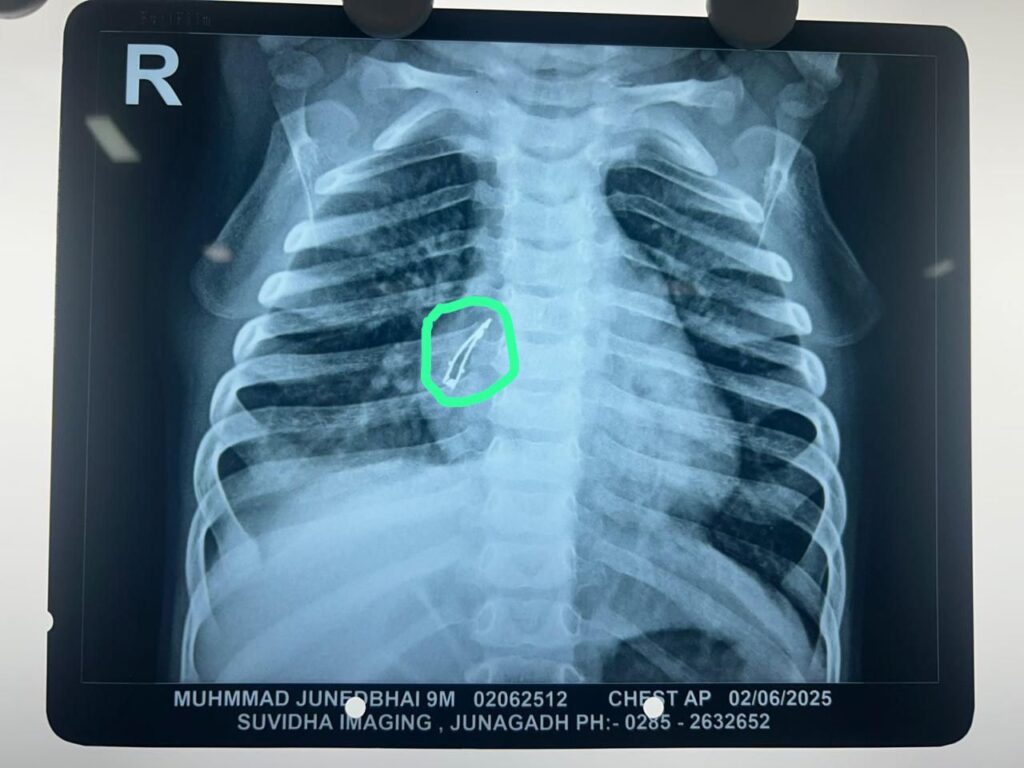

હોસ્પિટલમાં ડોક્ટરોએ જ્યારે બાળકની તપાસ કરી અને એક્સ-રે (X-ray) પાડ્યો, ત્યારે તેઓ પણ ચોંકી ગયા. એક્સ-રેમાં બાળકની જમણી બાજુની શ્વાસનળીમાં એક ધાતુ જેવી વસ્તુ દેખાતી હતી. તે બીજું કંઈ નહીં પણ પેલો LED Bulb હતો. આ સ્થિતિ મેડિકલ ભાષામાં અત્યંત ઇમરજન્સી ગણાય છે કારણ કે તે શ્વાસનો માર્ગ રોકી રહી હતી.